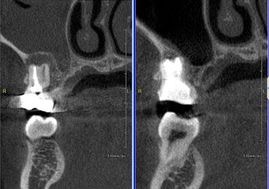

マイクロとCTを使用し根管治療行った症例

CTにてBM2根の存在を確認しマイクロで探索。

骨吸収の改善と根尖病巣からの上顎洞の炎症も改善している。